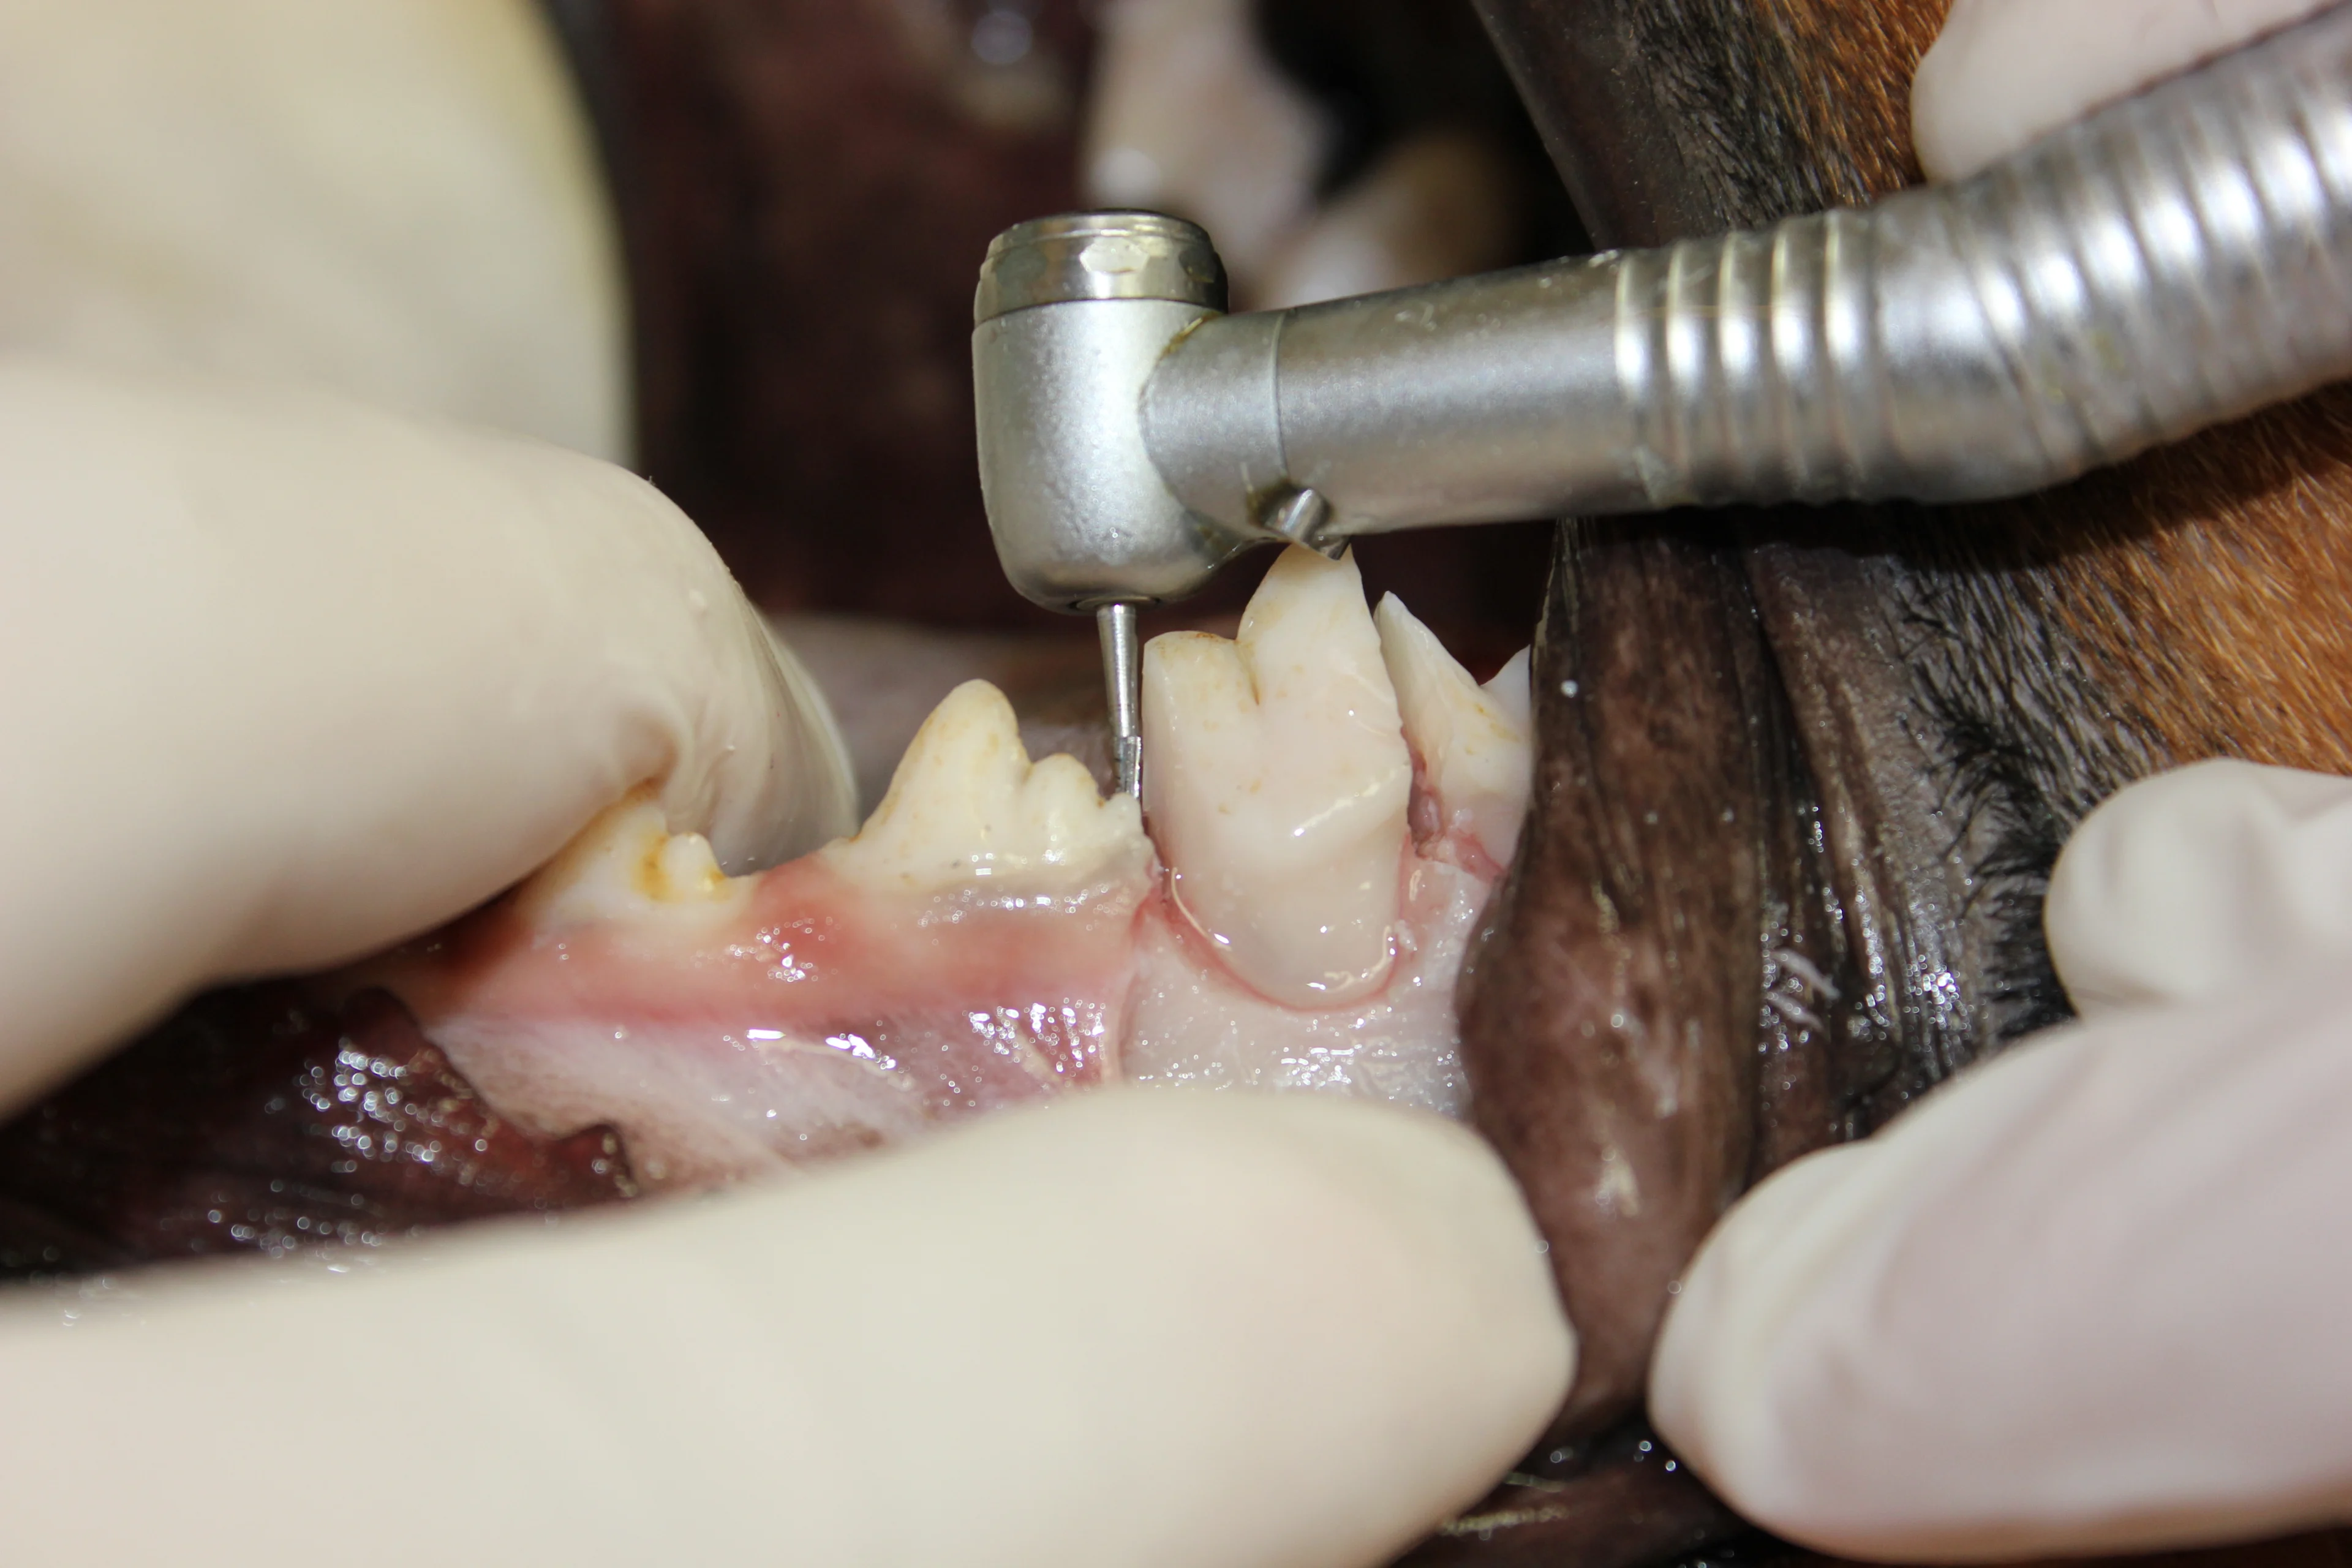

Use a #8 round bur in a water-cooled high-speed handpiece with light pressure to remove the alveolar bone and expose the furcation.

Round burs range in size from #2 to #8, increasing in size with the number. Bur size is selected based on the size of the patient.

(A) Section the tooth at the furcation with a #701L bur (cross-cut taper fissure bur) in the water-cooled high-speed handpiece. Place the bur in the furcation perpendicular to the root axis. Once the bur has passed through the alveolar bone, advance it in a coronal direction until it is completely through the crown. (B) To determine complete section of the crown, place a dental elevator between the sectioned segments and rotate it gently. If the 2 segments move independently, the crown has been completely sectioned.